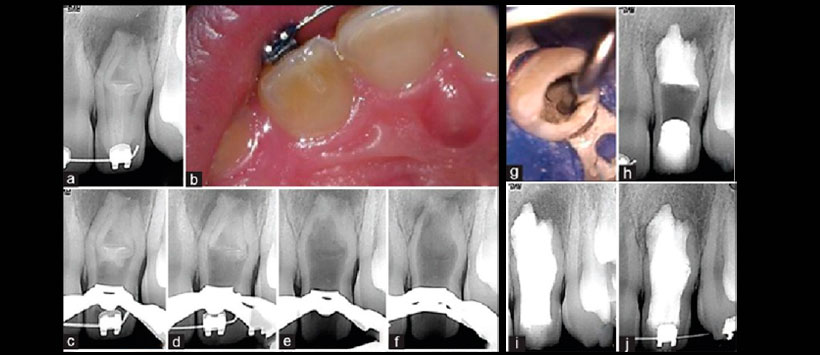

Figura 2: Tratamiento de pieza 1.2. a) Radiografía periapical preoperatoria, b) Foto del acceso inicial al dens in dente que muestra la pulpa vital. C) determinación de la longitud de trabajo, d) eliminación ultrasónica del dens, e) radiografía de eliminación del dens, e) confirmación radiográfica de colocación del MTA en el tercio apical, g) fotografía de la colocación de postes de fibra, h) fotografía de la cementación de los postes de fibra, i) restauración final, j) radiografía post-operatoria, k) control a los 12 meses, l) control a los 24 meses.